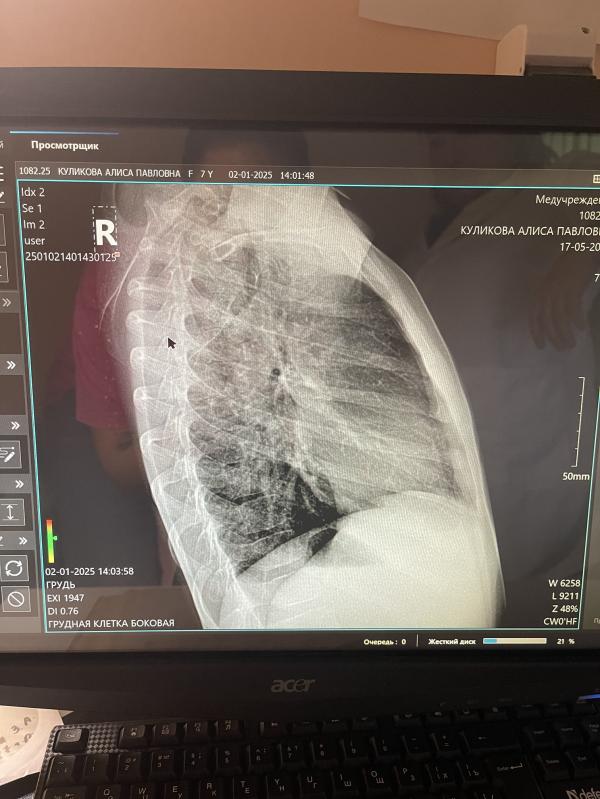

По рентгену поставили дочке бронхитическую картину легких.

Но мне написали,что очень положе на пневмонию.

Рентген видит пневмонию. А какая она определяется анализом крови.

Пневмонии по снимку нет